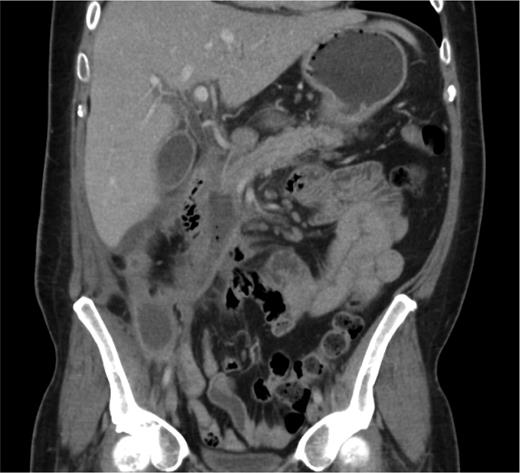

A coronal CT image 12 weeks following his initial presentation with necrotizing pancreatitis; there is atrophy of the pancreatic head and a fluid collection tracks caudally to the right iliac fossa wound. Small bubbles of gas are also seen within the fluid collection. The pancreatic duct is visible and of normal calibre.

On the 16th day, beige fluid began to discharge from the appendicectomy wound. The amylase level of this fluid was 18 240 IU/l, suggesting the presence of a pancreatic fistula emerging via the appendicectomy wound (see Fig. 1). A decision was made to treat the fistula conservatively. Octreotide was administered and the patient was fed parenterally, and later enterally. Abdominal collections were drained percutaneously on a number of occasions under radiological guidance. Serial CT scans continued to confirm that necrosis was limited to the head of the pancreas, the body and tail enhanced healthily. Fluid collections were seen especially in the right paracolic area compatible with a fistulous track and drains inserted into this area on several occasions. However, this never significantly affected the persistent fistulous output through the appendicectomy wound which remained between 150 and 250 ml per day. After ∼8 weeks, the patient improved enough to be managed with regular home leave; however, he did remain significantly nauseated and had a low mood throughout this period.